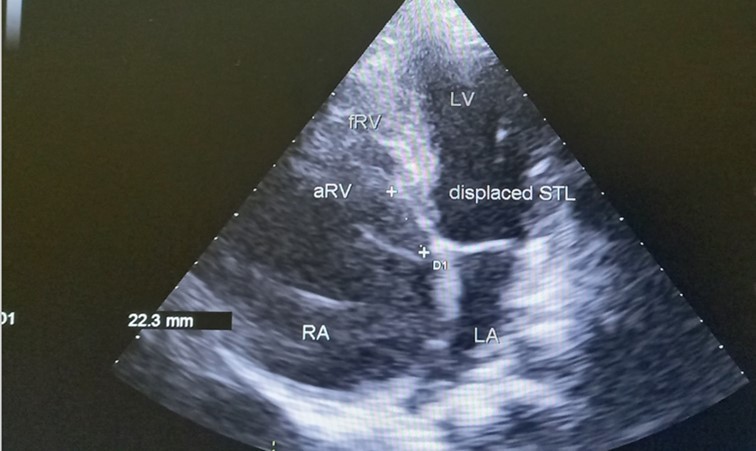

The patient underwent echocardiography (Figure 3 ) showing a low insertion of the septal and posterior leaflets of the tricuspid valve 22 mm below the tricuspid annulus, the anterior leaflet having reduced reduced mobility. Significant dilatation of the the right atrium by atrialisation of the right ventricle (RV). The rudimentary RV and its atrial stump are dilated and responsible for compression of the LV. There was no tricuspid insufficiency. No other associated congenital anomaly. However, we found a large floating thrombus in the right atrium measuring 64 mm x 30 mm in diameter. This was therefore Ebstein's disease at stage C of the Carpentier classification. The apical displacement of the tricuspid septal valve was 22 mm or 15 mm/m2). The surface area of the atrium and the atrialized right ventricle was 45 cm2 , the surface area of the right ventricle and the left cavities was 30 cm2 , the Celermajer index was calculated at 1.4 ( Grade 3).

Figure 3.Transthoracic echocardiography, apical four chambers view . Apical displacement of the tricuspid valve (a) and right atrial thrombus (b).

Transthoracic echocardiography, apical four chambers view . Apical displacement of the tricuspid valve (a) and right atrial thrombus (b).

Echocardiography is an essential diagnostic test and allows accurate assessment of the tricuspid valve leaflets and the size and function of the heart chambers. The main feature of Ebstein’s anomaly is an apical displacement of the tricuspid septal leaflet of at least 8 mm/m2. The average displacement in our patient was 15 mm/m2